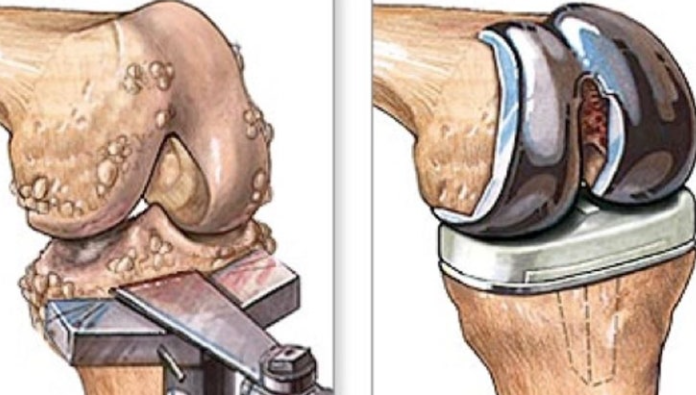

1. 무릎 인공관절 수술이란?

무릎 인공관절 수술은 퇴행성 관절염이나 관절 손상으로 인해 정상적인 생활이 어려운 분들을 위해 손상된 관절을 금속 또는 플라스틱 인공관절로 치환하는 수술입니다.

- 일반적으로 치환술이라고도 하며, 전치환(전체 교체)과 부분 치환술로 나뉩니다.